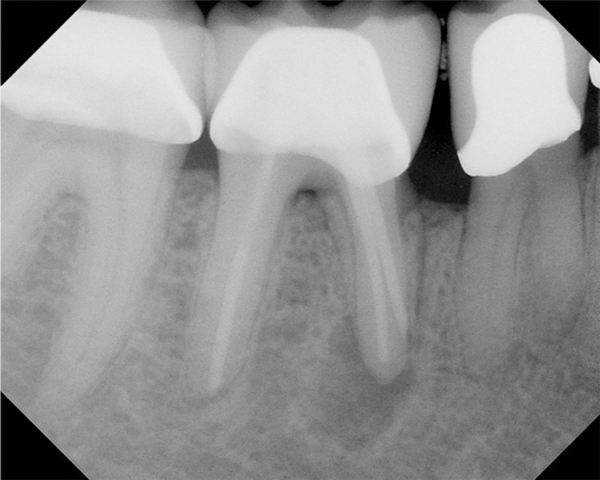

Fig 11. Preoperative radiograph. Courtesy of Dr. Guillaume Jouanny.

Figure 11

Fig 12. Postoperative radiography after full pulpotomy was performed. Courtesy of Dr. Guillaume Jouanny.

Figure 12

Fig 13. Tooth was asymptomatic at 1-year follow-up. Courtesy of Dr. Guillaume Jouanny.

Figure 13

Fig 14. Contralateral tooth at 1-year follow-up. Courtesy of Dr. Guillaume Jouanny.

Figure 14

In this case, the tooth tested vital but showed clinical signs of irreversible pulpitis. Treatment with a full pulpotomy was chosen to improve the chances the remaining pulp would survive and remain healthy. The preoperative radiograph in Figure 11 shows extensive caries in the tooth and a slightly widened apical periodontal ligament. A full pulpotomy was performed using the BC putty (Figure 12). After the putty set, a coronal restoration was placed, and an immediate postoperative radiograph was taken and viewed. At the 1-year follow-up, the tooth was asymptomatic, and the radiograph showed continued root development (Figure 13), a healthy apical periodontium, and, importantly, no calcifications in the remaining pulp (as is often seen with a calcium hydroxide therapy). A radiograph taken of the contra-lateral tooth showed similar root development (Figure 14).